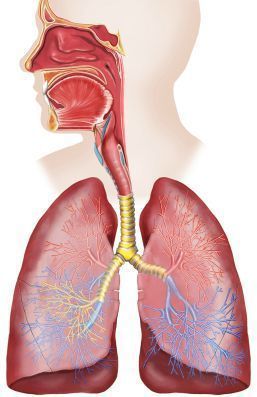

Sistema Respiratorio. Selecciona La Opción Correcta: